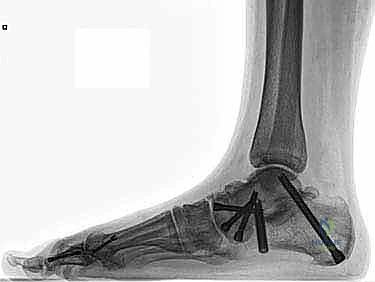

* الإصلاح المباشر (Direct Repair): إذا كانت أنسجة الرباط الممزقة ذات جودة جيدة (عادة في الإصابات الحديثة)، يقوم الدكتور هطيف بخياطتها مباشرة. يستخدم خطاطيف تثبيت عظمية (Suture Anchors) صغيرة جداً ومصنوعة من مواد متوافقة حيوياً (تذوب مع الوقت أو من التيتانيوم) لغرس الخيوط القوية في عظمة الكعب الإنسي، ثم يتم سحب الرباط الممزق وتثبيته بقوة في مكانه التشريحي الأصلي.

- إعادة البناء (Reconstruction): في الحالات المزمنة حيث يكون الرباط الأصلي قد تليف، تآكل، أو أصبح غير كافٍ للاستخدام، يلجأ الدكتور هطيف إلى تقنية "إعادة البناء". تتضمن هذه التقنية المتقدمة استخدام رقعة وترية (Graft)، إما من جسم المريض نفسه (Autograft - مثل أوتار الركبة أو وتر من القدم) أو رقعة صناعية متطورة. يتم حفر أنفاق ع